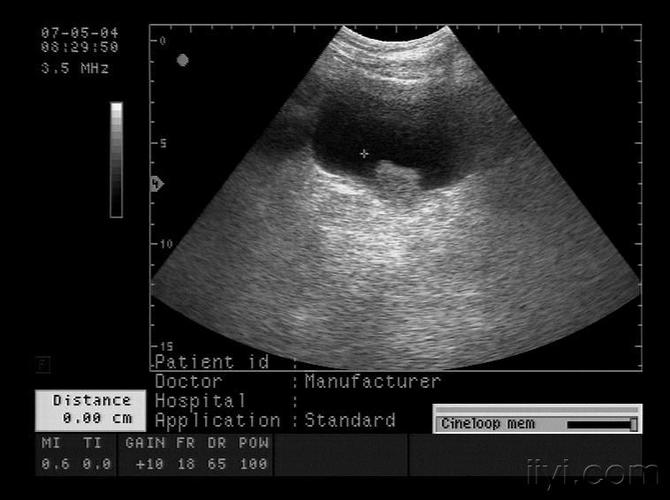

典型膀胱占位两例!(膀胱癌)

膀胱占位

这是膀胱占位吗?